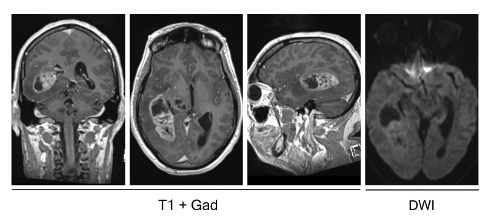

Chẩn đoán u nguyên bào thần kinh đệm được xác định bằng cách sử dụng các phương pháp chẩn đoán hình ảnh như MRI, CT scan và xét nghiệm tế bào u. MRI là phương pháp chẩn đoán tốt nhất để xác định u nguyên bào thần kinh đệm.